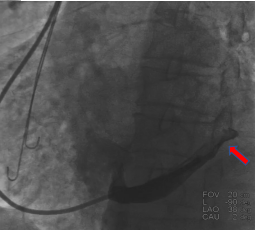

鞘管进入窦口之后冒烟显示静脉有部分狭窄,球囊造影的时候也出现阻力,造影显示近端有瓣,无法通过电极,最终利用球囊扩张,让电极顺利通过静脉瓣。

图五&六 造影发现有静脉瓣

图七 预扩球囊扩张血管